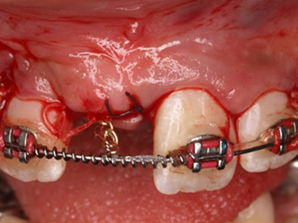

Răng thừa (a) làm R11 (b) bị kẹt không mọc ra được Tạo khoảng trước phẫu thuật

Phẫu thuật lấy răng thừa sau 4 tháng tạo khoảng Chỉnh nha kéo R11 ngầm lên

Qúa trình chỉnh nha kéo răng cửa mọc ngầm hoàn tất

Hình 5: Minh họa phẫu thuật lấy răng thừa kết hợp với chỉnh nha ở một bé trai 9 tuổi